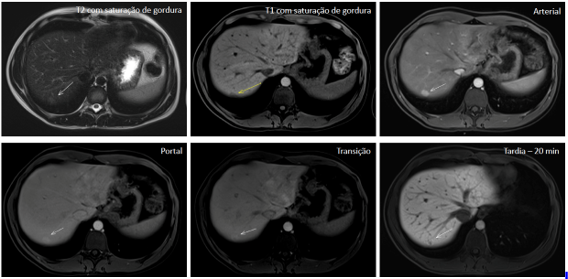

<content:encoded><![CDATA[<p>Rutinariamente, en la resonancia magnética (RM) del abdomen, se utiliza el contraste extracelular inespecífico (gadolinio), que se distribuye de acuerdo con la distribución de los vasos y capilares sanguíneos y determina, así, un patrón dinámico de impregnación de la lesión focal hepática en las fases arterial, portal (venosa) y equilibrio.</p>

<p>En casos seleccionados, se pueden indicar los contrastes intracelulares específicos, también denominados de hepato-específicos y que pueden ser de dos clases principales: (1) óxido de hierro superparamagnético y (2) hepatobiliares, siendo este último captado específicamente por las células hepáticas y con excreción renal (50%) y biliar (50%). En Brasil, está aprobado el contraste hepatobiliar, conocido como ácido gadoxético (Gd-EOB-DTPA, PrimovistÒ).</p>

<p>De esta manera, además de proporcionar los datos habituales del estudio dinámico, existe la etapa final de evaluación hepatobiliar, después de aproximadamente 10 a 20 minutos de la inyección endovenosa, en la cual el contraste entra en los hepatocitos a través de los transportadores de membrana (OATP1, B1/B3) y sale a través de proteínas dependientes de ATP resistentes a múltiples fármacos (MRP2, MRP3, MRP4), siendo el transportador MRP2 el encargado de excretar el contraste en el canalículo biliar.</p>

<h2 class="wp-block-heading"><strong>¿Cuáles son las indicaciones del contraste hepatobiliar?</strong></h2>

<p>Sabiendo que el ácido gadoxético es captado por los hepatocitos y excretado en aproximadamente un 50% por la vía biliar, se espera que un tejido hepático normofuncionante sea impregnado por el contraste en la fase hepatobiliar. De esta manera, la no captación del ácido gadoxético en la fase hepatobiliar infiere que no hay hepatocitos o canalículos biliares viables en la lesión evaluada.</p>

<p>Podemos enumerar 3 indicaciones principales en el uso del ácido gadoxético en la evaluación de lesiones focales hepáticas:</p>

<h3 class="wp-block-heading">1. <strong>Diferenciación entre hiperplasia nodular focal (HNF) y adenoma</strong></h3>

<p>El adenoma y la HNF son el tercer y segundo tumores hepáticos benignos más frecuentes, respectivamente.</p>

<p>El adenoma se caracteriza por cordones de hepatocitos y ausencia de conductos biliares o tractos portales, por lo tanto, no presenta captación en la fase hepatobiliar.</p>